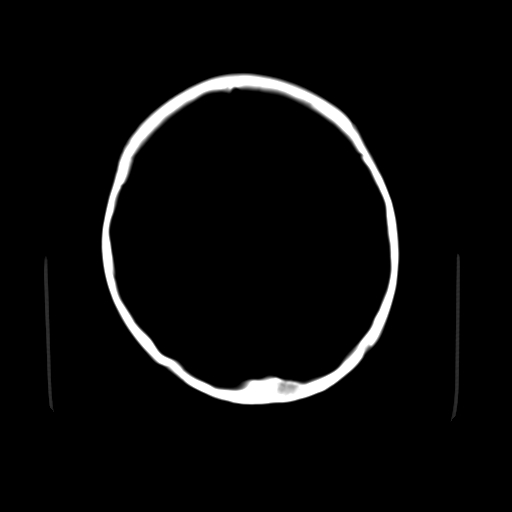

猜一个:左枕骨嗜酸性肉芽肿?但不具膨胀性,难说

考虑枕骨血管瘤

颅内未见明显异常,枕骨松质骨瘤可能性大。颅骨板障起源骨瘤较常见,骨血管瘤有垂直骨针及粗大钙化,嗜酸性肉芽肿软组织有改变,典型者可见“纽扣状”死骨,年龄通常较小。

良性骨肿瘤或肿瘤样病变

枕骨松质骨良性病变。

左枕骨松质骨不均匀低密度灶,边缘清楚,考虑良性松质骨性骨瘤可能性大。

以下是引用sunbin在2010-1-6 14:39:00的发言:[br]左枕骨松质骨不均匀低密度灶,边缘清楚,考虑良性松质骨性骨瘤可能性大。

不排除左枕骨嗜酸性肉芽肿可能。